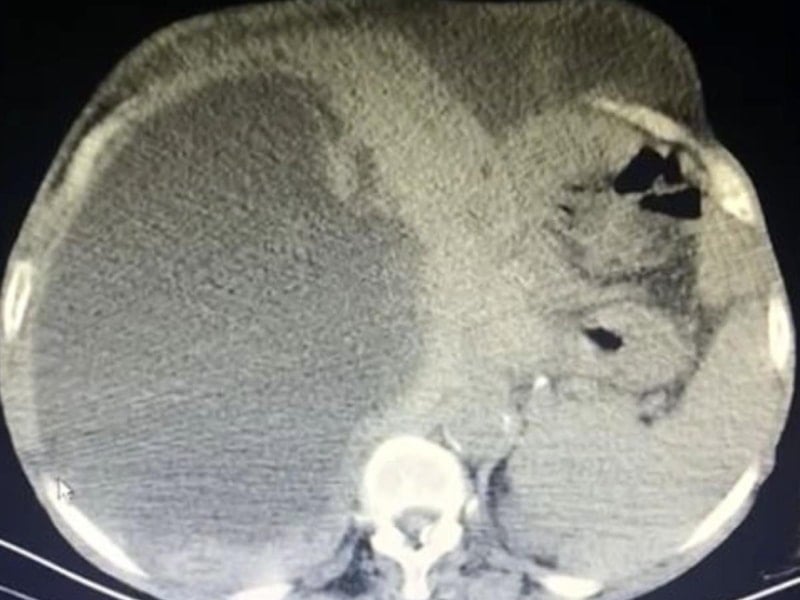

Taşdelen’e sağlık görevlileri tarafından yapılan muayene ve görüntüleme tetkiklerinde karaciğerinde, 90 santimetreye ulaşarak karnını kaplayan 3 ayrı kedi-köpek kisti saptandı.

Dünya literatüründe 90 santimetreye ulaşarak tüm karnı dolduran bir kist ile ilk kez karşılaşıldığını ifade eden Dr. Çelik, kedi-köpek kisti olarak bilinen hastalığın bulaşma yollarını anlattı.

O hastalıkları ekarte edebilmek için ilgili branşlarla birlikte vakayı değerlendirdik. Hastamızın ameliyat olabilirliğini tartıştık. Konsey kararı ile ameliyatına karar verdik. Hastamızın karaciğerinde 3 ayrı kist vardı. Tüm karnı kist ile kaplıydı. 2 tanesinin tamamına çıkardık. Diğerini ise kontrole alarak içini boşalttık.

Dünya literatüründe 90 santimetreye ulaşarak tüm karnı dolduran kist görmedik. Ameliyatımız 2 saat sürdü. Hastamızın safra yolları kontrol edildi. Hastamızın durumu gayet iyi. Solunum cihazından bağımsız olarak kendi başına solunum yapabiliyor. Yarın da servise alacağız.